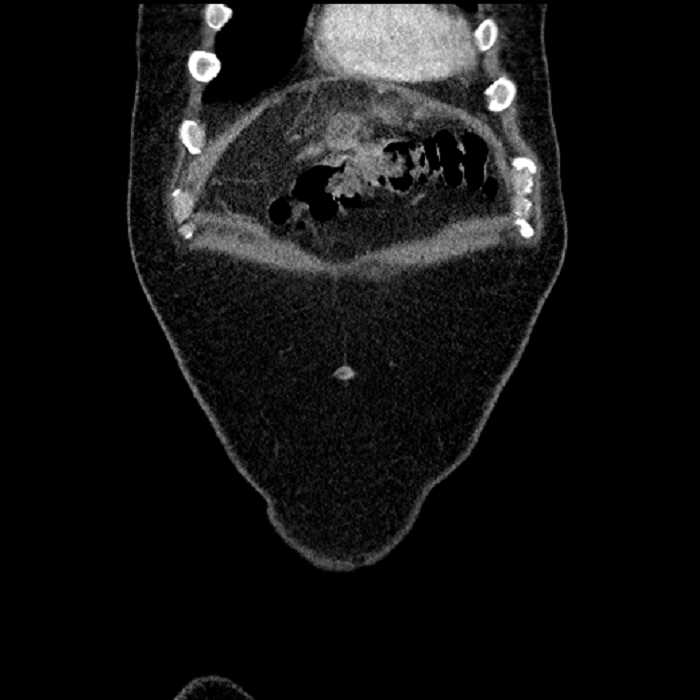

• Large fluid density structure in hepatic segments 7 and 8 measuring 10 x 7 x 7 cm with internal septation and circumferential ill-defined low density compatible with edema

• Peripherally enhancing subcapsular collections along the anterior margin of the left hepatic lobe measuring 3 x 1 cm and 2 x 1 cm

• Clearly marginated fluid density structure in segment 7 and several other scattered tiny hypodensities, which likely represent cysts

• High grade stenosis of the left common iliac artery, with the left internal and external iliac arteries remaining patent

Acute sigmoid diverticulitis complicated by a small contained perforation and a large abscess in the right hepatic lobe. Additional small subcapsular abscesses along the anterior margin of the left hepatic lobe.

• The classic CT imaging appearance is a double target sign with internal low density surrounded by an internal enhancing rim (capsule) and a low density external rim (edema)

Hepatic abscess showing the double target sign with low density internally surrounded by a thin inner enhancing rim (red arrow) and ill-defined outer low density rim (yellow arrow). Blue arrow indicates an internal septation. Red arrows: additional smaller subcapsular abscesses. Red arrow: focal contained perforation associated with diverticulitis.